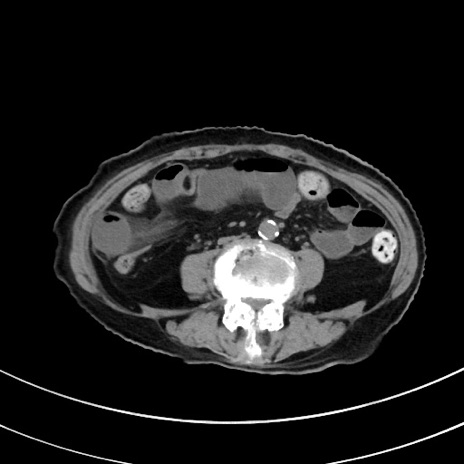

症例33(横断像)

【症例】70歳代 女性

【主訴】心窩部痛

【現病歴】延髄病変の精査・加療にて神経内科入院中。本日より心窩部痛あり。

【既往歴】虫垂炎

【身体所見】右下腹部を中心に圧痛と反跳痛あり。

【データ】WBC 10900、CRP 0.02